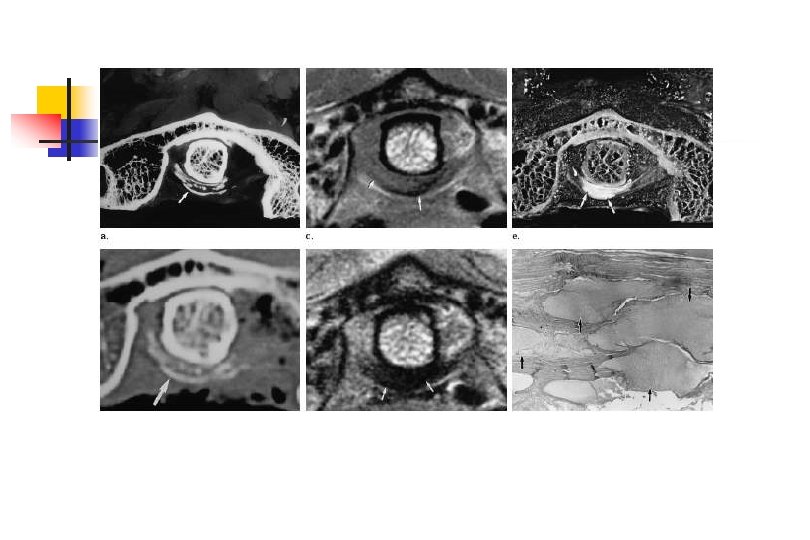

CPPD: Periartikülar ve Aksiyel Tutulum CPPD: Periartikülar ve Aksiyel Tutulum

CPPD: Tümoral Kitle CPPD: Tümoral Kitle

CPPD: Tanı CPPD: Tanı